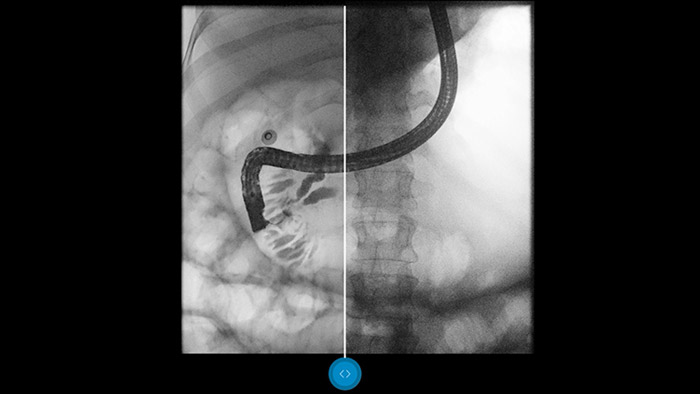

See Dynamic UNIQUE at work

Compare side-by-side with a conventional image processing and see the benefits for yourself.

Dynamic UNIQUE features intelligent spatiotemporal noise suppression, temporal brightness stabilization, and real-time multiscale image enhancement, to permit high-quality image processing in real-time.